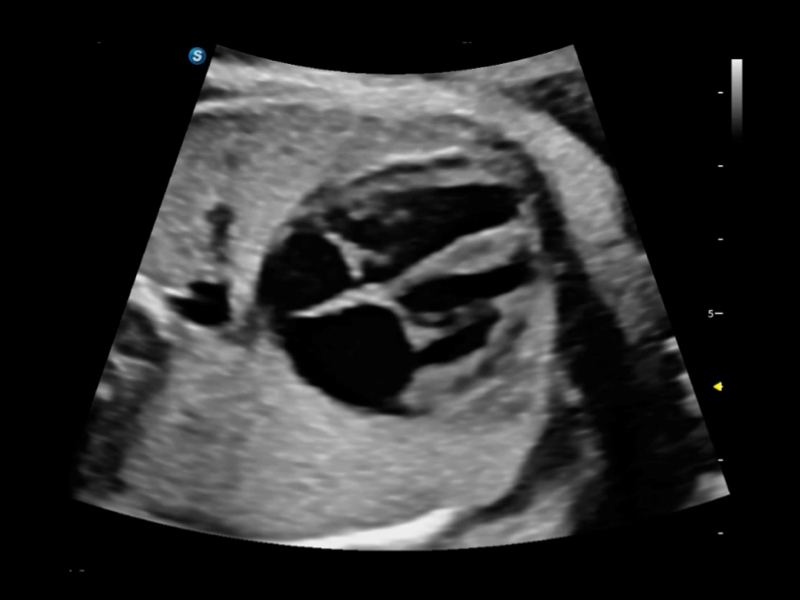

S80 提供多樣化超聲成像技術(shù),可滿足不同科室的需求,在助力掃查診斷和介入治療中發(fā)揮著重要作用。

提供解剖示意圖、標(biāo)準(zhǔn)超聲圖像、掃查手法圖和操作者實(shí)時(shí)檢查圖像,指導(dǎo)操作者進(jìn)行標(biāo)準(zhǔn)切面的正確掃查。